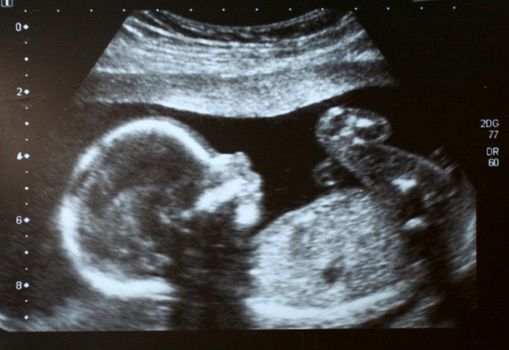

Everyone knows you should wait 12 weeks to tell your friends and family your good news, right?

But have you ever stopped to wonder why the magical number is 12 weeks?

Women who know they’re pregnant have a one-in-six chance of having a miscarriage… and the majority of miscarriages happen before the 12-week mark.